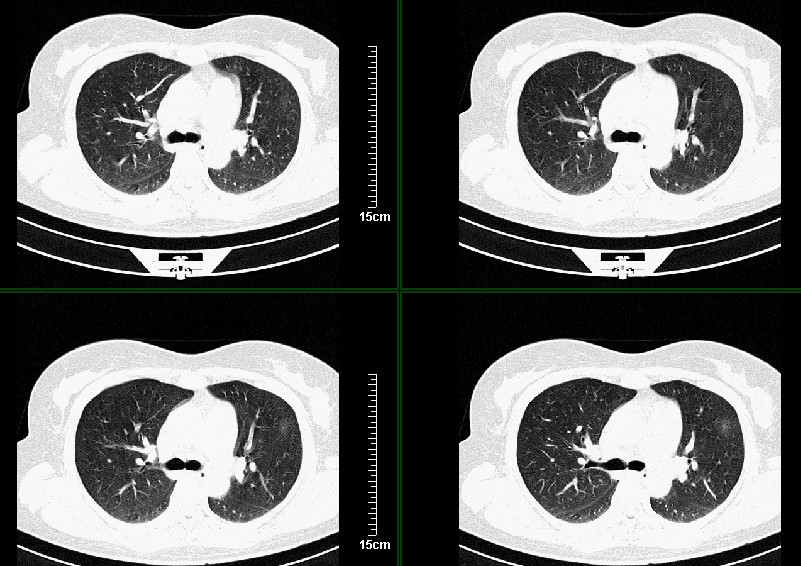

一周之后 复查结果 5mm扫描 40多岁 我们医院的护士

左肺上叶肿块,肺窗周围有“晕征”,纵隔窗有毛刺,临床资料???只能考虑占位???

第八幅图像,典型毛刺,像日本鬼子的膏药军旗一样,一看就不是个好东西